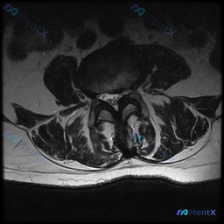

这是一份腰椎MRI的T2加权轴位(横断面)扫描,层面位于腰椎间盘层面,可观察到的结构包括:前方椎体后缘、中部椎管内含硬膜囊、双侧关节突关节、后方椎板棘突以及两侧背肌。

- 椎间盘改变:椎间盘后缘向椎管内对称性膨隆,超出椎体后缘边缘;椎间盘信号呈低信号(黑灰色),和正常髓核高信号相比明显减低,提示髓核脱水退变

- 椎管改变:硬膜囊前方受压,前后径变窄、形态轻度变形;双侧侧隐窝因为椎间盘膨出+关节突增生,空间明显受限

- 骨性结构与韧带:双侧关节突关节面骨质增生、关节间隙模糊、关节突肥大,属于典型退行性改变;黄韧带没有明显极度肥厚或钙化,但和增生的关节突共同对椎管后外侧形成压迫;未见明显椎体后缘骨赘